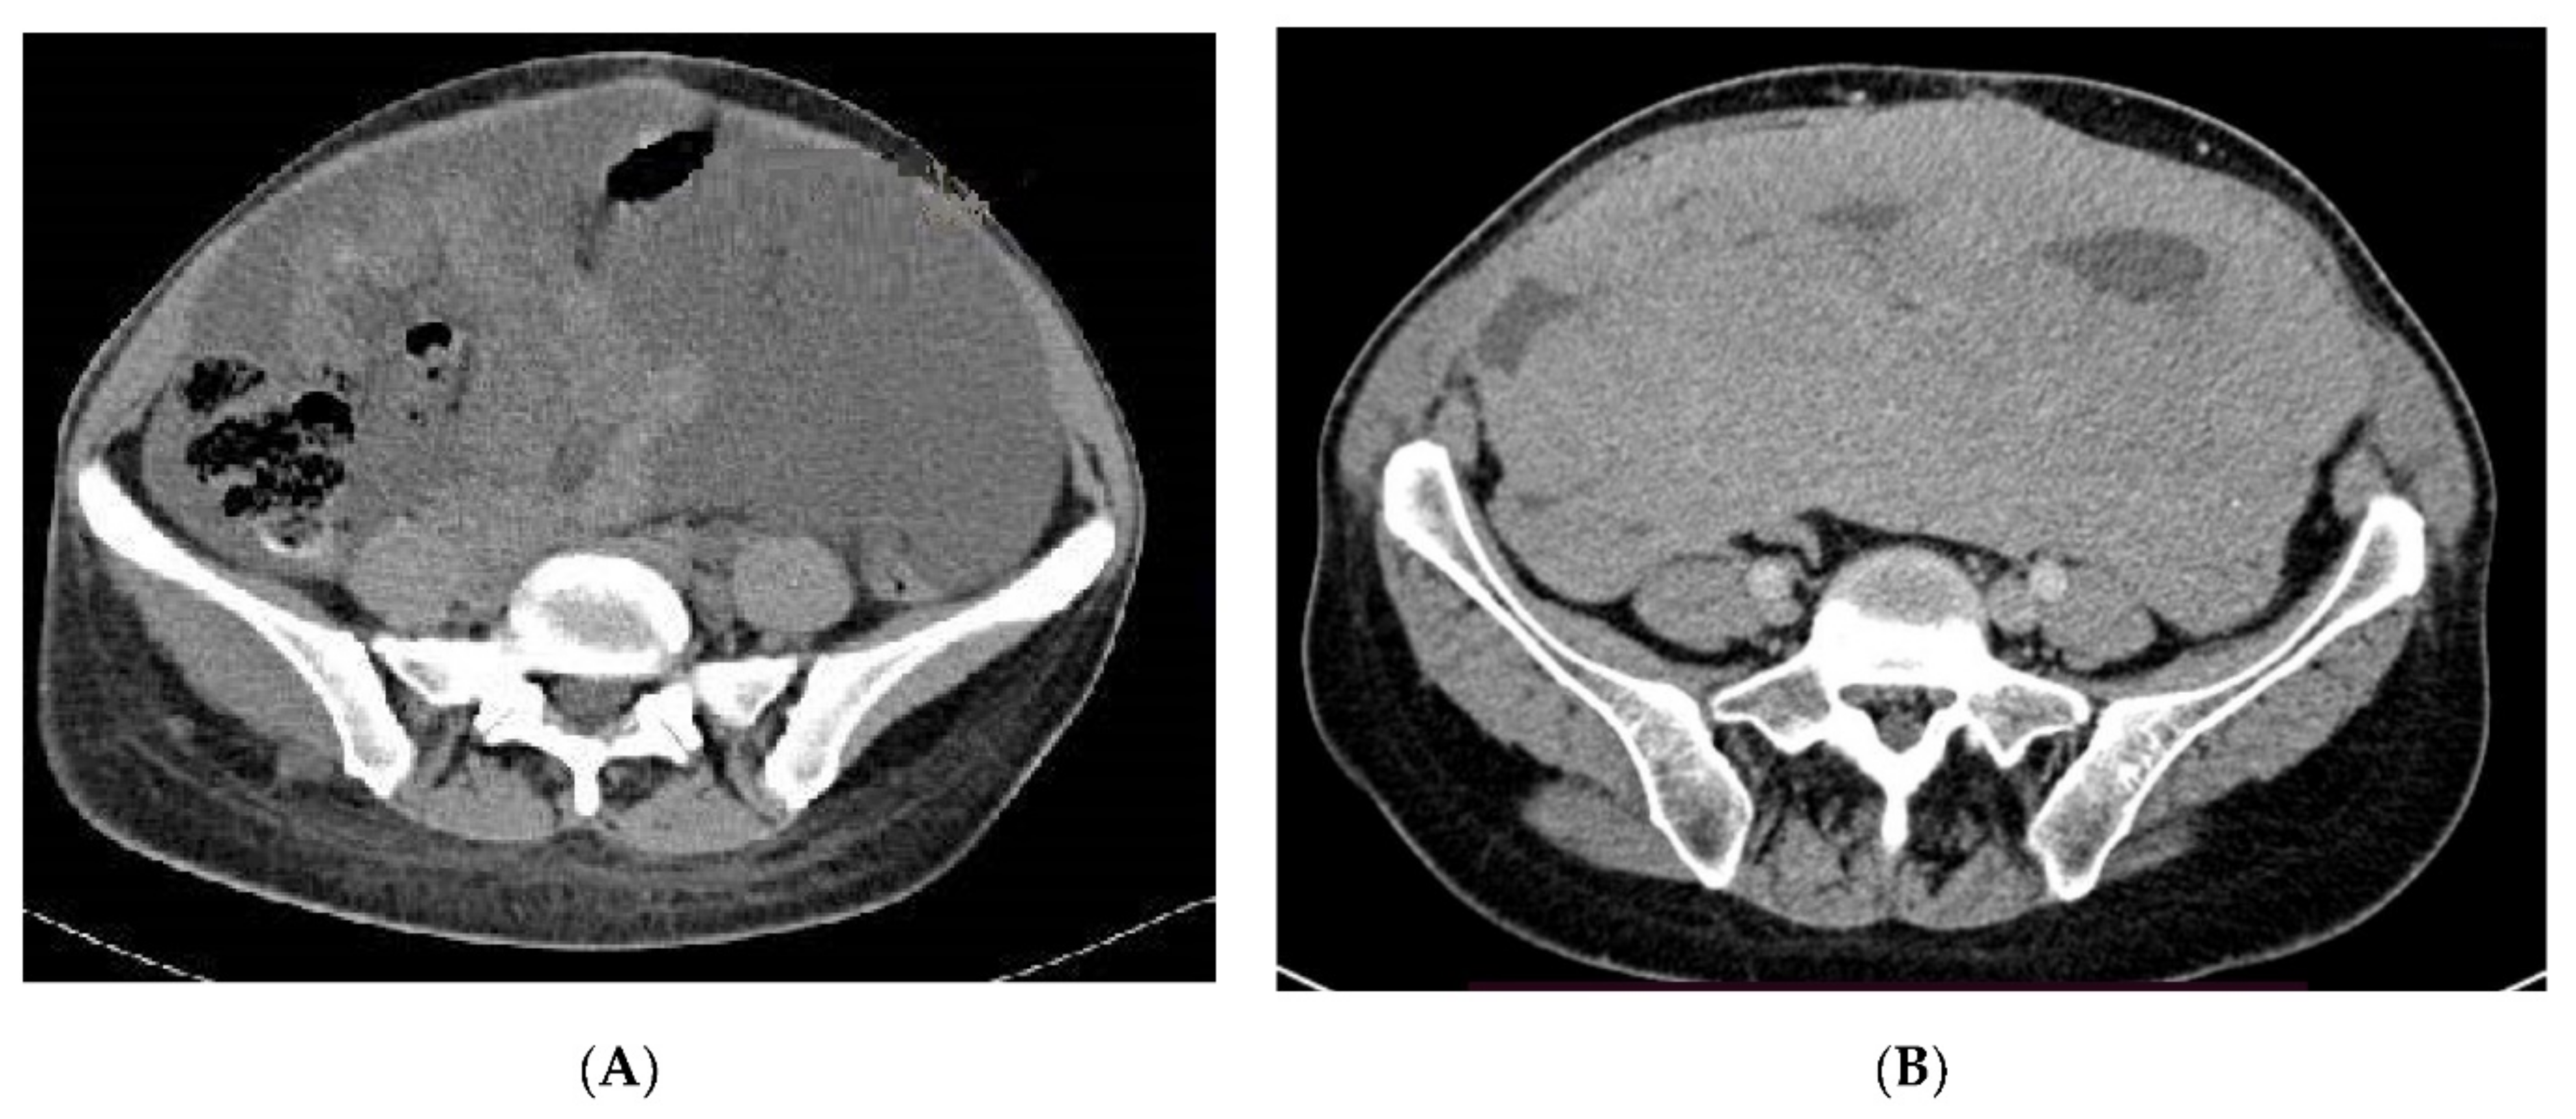

- Tirumani, S.H.; Shinagare, A.B.; Hargreaves, J.; Jagannathan, J.P.; Hornick, J.L.; Wagner, A.J.; Ramaiya, N.H. Imaging features of primary and metastatic malignant perivascular epithelioid cell tumors. AJR Am. J. Roentgenol. 2014, 202, 252–258. [Google Scholar] [CrossRef] [PubMed]